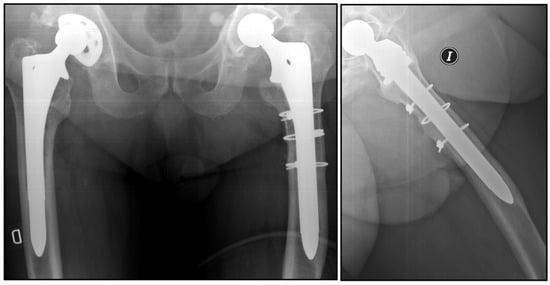

Comparison of Cylindrical and Tapered Stem Designs for Femoral Revision Hip Arthroplasty

2. Materials and Methods

2.2. Radiological Analysis

| Femoral osteotomy (n) | ||

| Not needed | 19 | 27 |

| Trochanteric | 8 | 2 |

| ETO 4 | 11 | 11 |